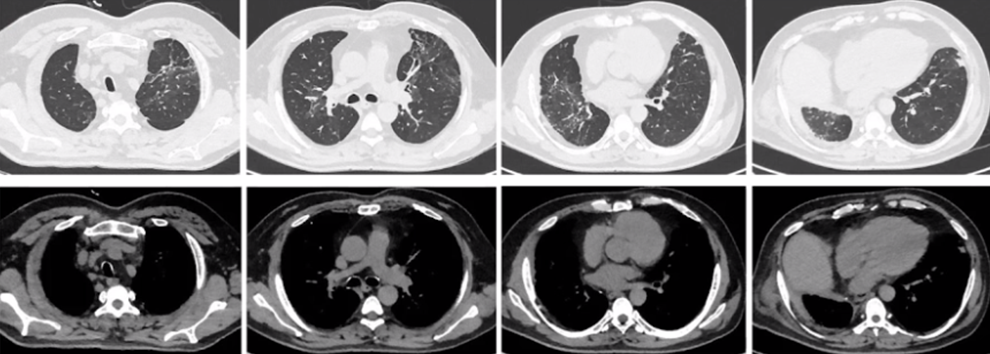

• 5月17日胸部CT:左肺病灶较前明显吸收,右肺上叶病变较前缩小(图9)。

图片

图9  患者胸部CT(2020年5月17日)

• 7月24日门诊复查胸部CT:病灶基本吸收,残留少许条索影和莫玻璃影(图10)

图10 患者胸部CT(2020年7月24日)

• 2021年3月24日门诊复查胸部CT:病灶较前进一步吸收好转(图11)

图11  患者胸部CT(2021年3月24日)